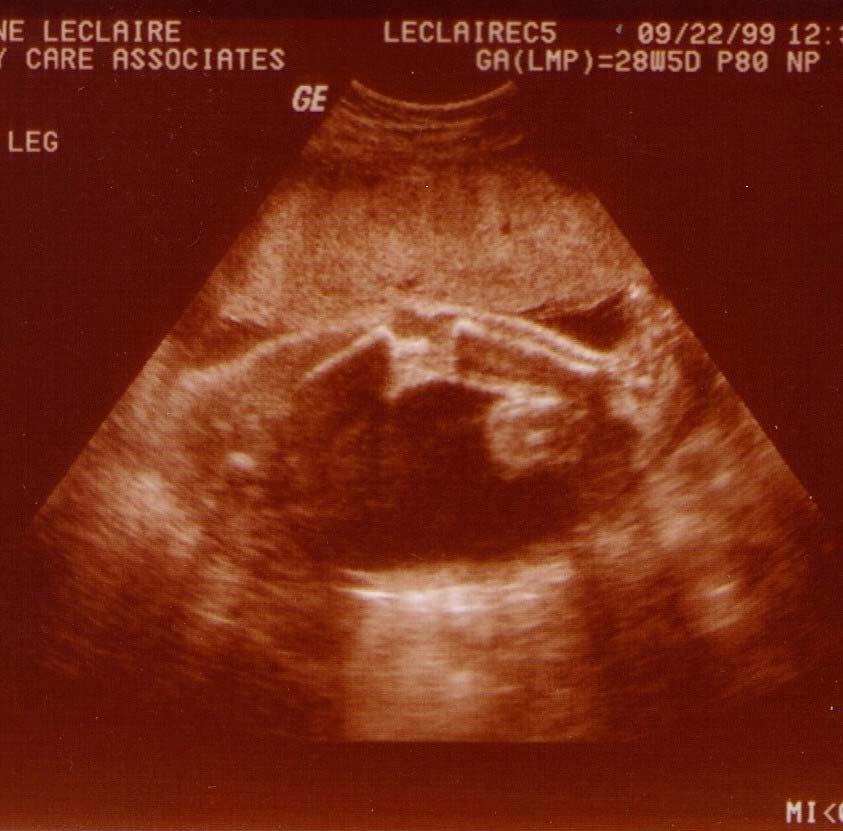

Alexander James LeClaire

Ultrasound Pics!